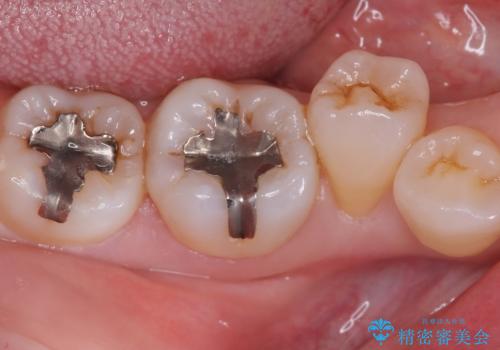

下顎大臼歯部に入っている保険適用のメタルインレーを、適合性と審美性の良いセラミックインレーでのやり替えとなりました。

メタルインレーを除去した際、古い裏層材やカリエスは除去し新たにCR裏層しています。